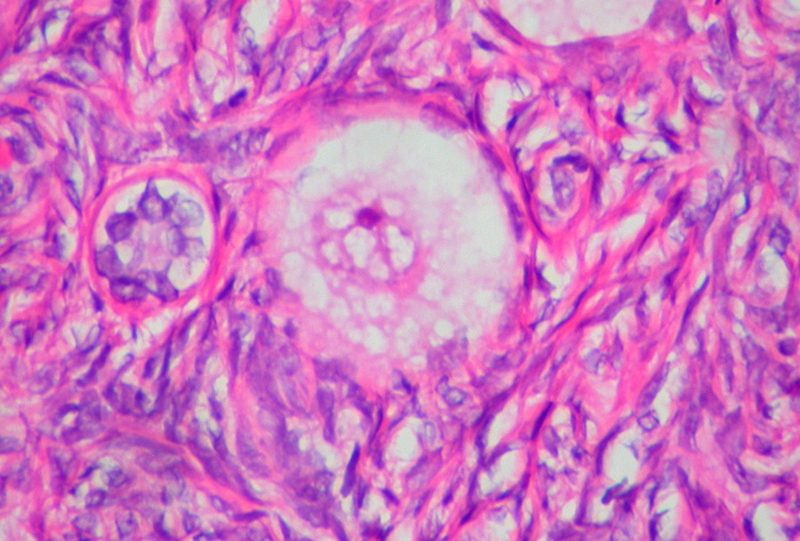

Foto di copertina di Ed Uthman (Flickr)